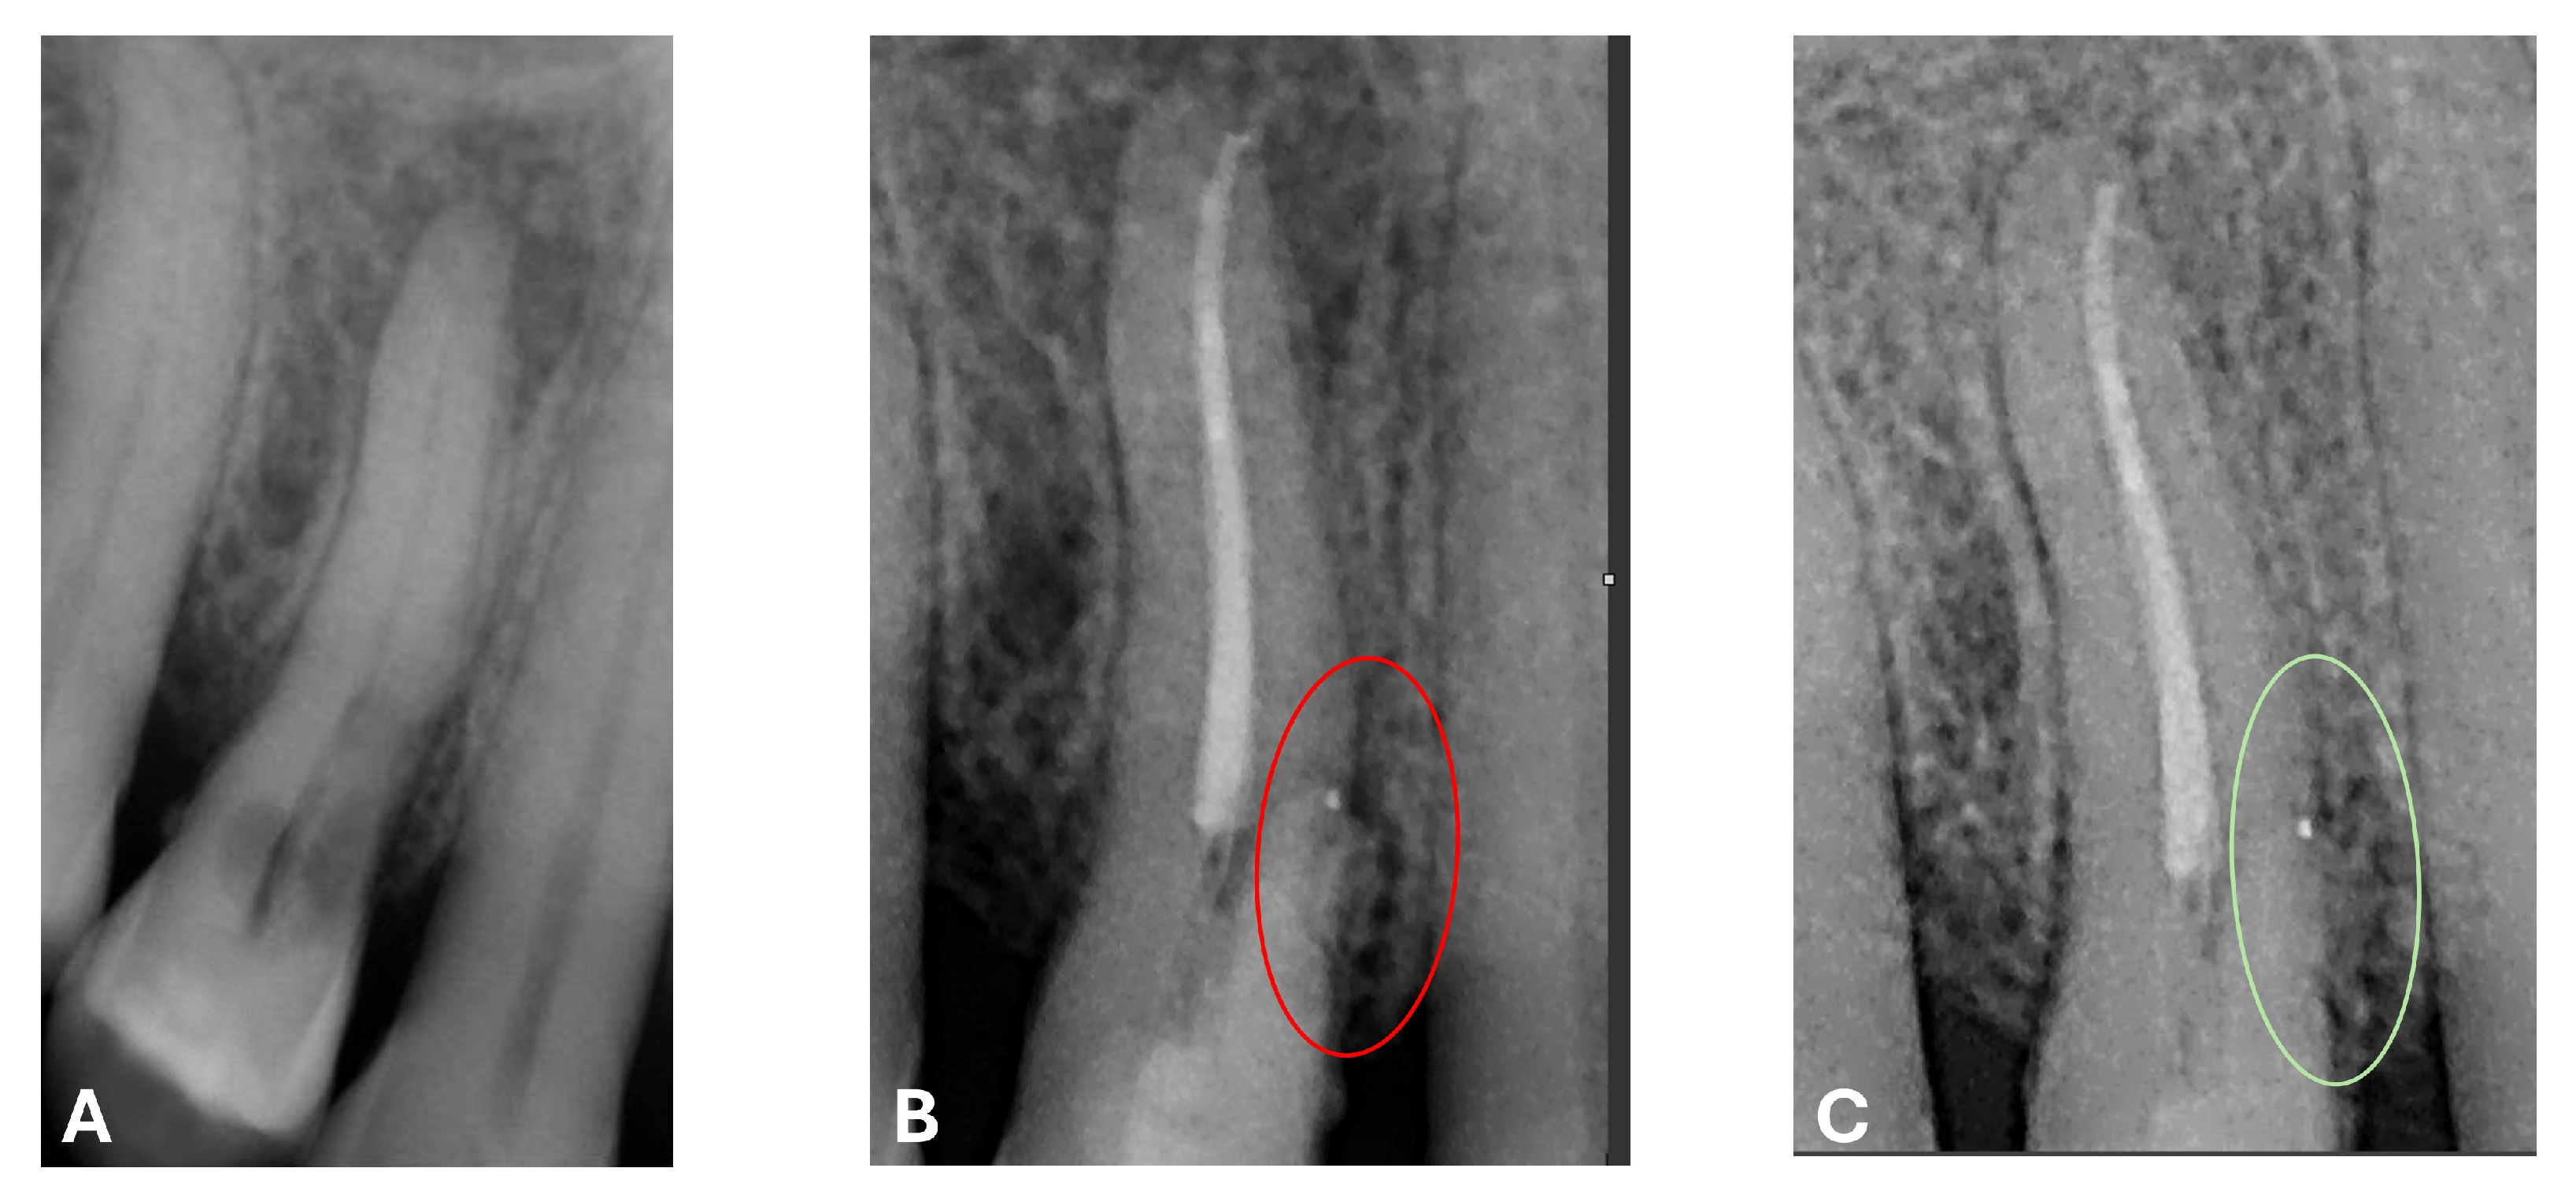

Signs of parafunctional habits and bruxism were noted, along with compromised periodontal status and poor oral hygiene. Multiple carious lesions were present, and the patient exhibited a gag reflex during examination. The patient presented complaining of spontaneous pain and pain upon mastication in the right maxillary region. Tooth 1.4 showed significant pain on percussion and a pathological periodontal probing depth at the mesiolingual site. Intraoral radiography revealed an extensive cervical root resorption zone and a periapical lesion (PL) (Figure 1).

Figure 1.

Intraoral radiography of tooth 1.4 showing root resorption, LP and EPL with mesiocervical widening of the lamina dura space.

At the 12-month radiographic follow-up, healing of the EPL was confirmed. Restoration of the lamina dura and the periodontal ligament adjacent to the treated site was observed (Figure 16 and Figure 17).

Figure 16.

Intraoral radiography of tooth 1.4 at 12-month follow-up.

Figure 17.

EPL before (A) and after treatment (red circle showing mesiocervical widening of the lamina dura space) (B) and at 12-month follow-up (C) with radiographic evidence of restoration of the lamina dura (green circle), periodontal ligament space and absence of PL.